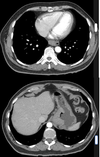

70 anos, masculino

Disfagia.

Leiomioma do esôfago

Neoplasias benignas do esôfago são raras (<1% dos tumores do esôfago)

TC: Massa intramural, bem definida, circunscrita, arredondada; densidade de partes moles; calcificação é quase patognomônico; realce difuso discreto / moderado pelo contraste.

Tumores pequenos < 5 cm geralmente são assintomáticos; tumores maiores podem causar disfagia, obstrução, tosse e sangramento.